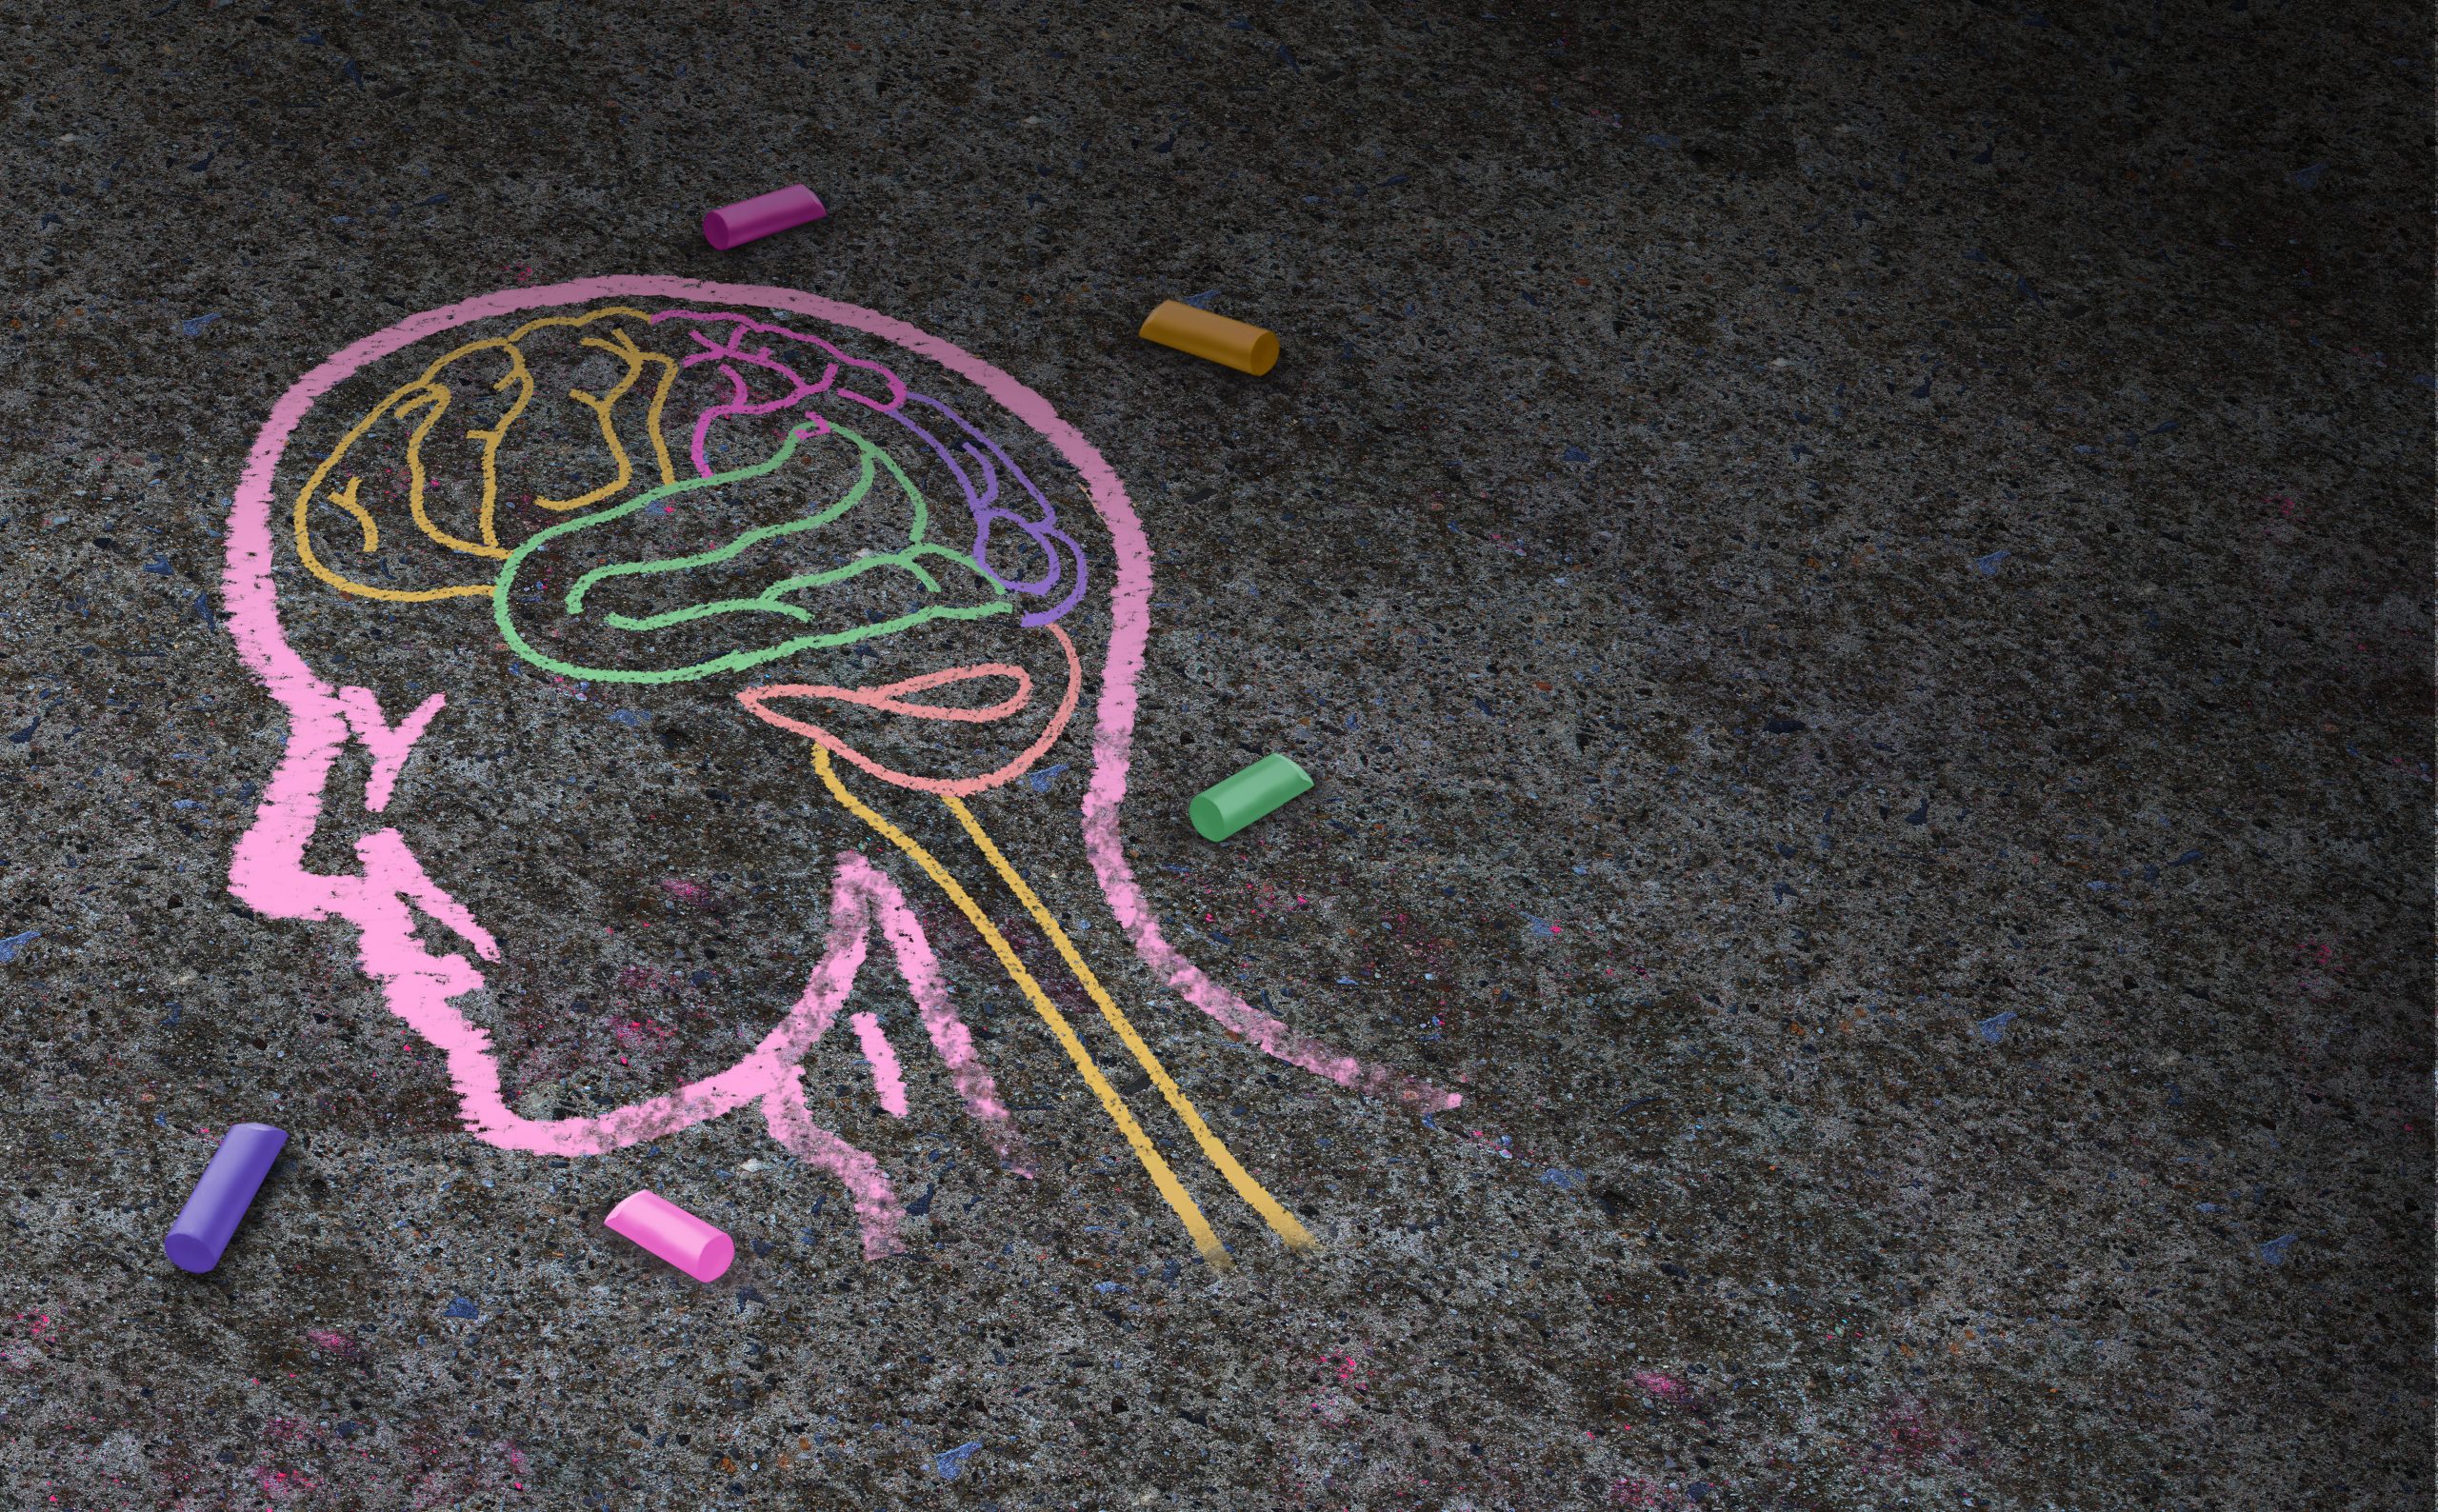

The Minder can slip beneath the scalp and monitor the brain.